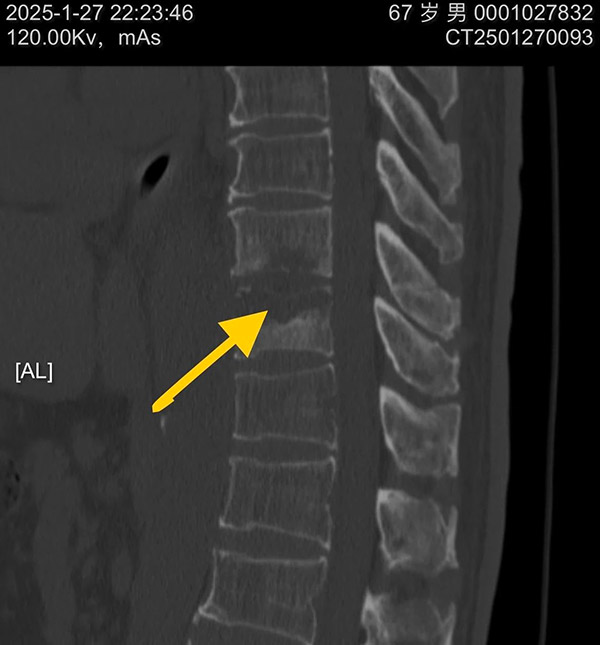

接到紧急通知后,脊柱外科的医生们迅速响应。他们告别了家中热闹的聚餐,告别了正在欢笑玩耍的孩子,告别了翘首以盼的亲人,第一时间赶回医院。此时,无影灯下,一场与时间赛跑的生命救援正式拉开帷幕。 手术台上,医生们全神贯注,每一个操作都精准而谨慎。他们深知,这场手术不仅关乎老人今后的生活质量,更关乎一个家庭的幸福。胸椎9 - 10椎体感染伴全瘫病灶清除减压手术难度极高,但脊柱外科的医护团队凭借着丰富的临床经验、扎实的专业知识和过人的心理素质,沉着应对每一个挑战。他们仔细地清除病灶,小心翼翼地进行减压操作,不放过任何一个可能影响手术效果的细节。 手术室外,老人的家属焦急地等待着,每一分每一秒都显得无比漫长。他们的眼神中充满了担忧和期待,心中默默祈祷着手术能够顺利成功。而医护人员的每一次沟通,都是给家属吃的定心丸,让他们在焦虑中感受到了一丝温暖和希望。 经过数小时的艰苦奋战,手术终于顺利完成。当医生们走出手术室,脸上虽然带着疲惫,但眼神中却透露出欣慰和自豪。他们成功地为老人清除了病灶,减轻了神经压迫,明确病因,为老人重新站起来带来了希望。这一刻,所有的付出都变得无比值得。 在术后的护理过程中,脊柱外科的护理团队时刻关注着老人的生命体征,精心照顾老人的生活起居。无论是按时为老人翻身、换药,还是耐心地安抚老人的情绪,她们都做得细致入微。大年初四早晨,术后第三天,老人的下肢感觉定位觉逐渐恢复,同时通过医院实验室的病原学培养明确为耐药金黄色葡萄球菌感染,为后续治疗指明了方向。随着症状逐渐好转,患者和家属的脸上都露出了久违的笑容。 沈阳市第十人民医院(沈阳市胸科医院)脊柱外科的全体医护人员,用实际行动诠释了医者仁心的深刻内涵。在这个特殊的春节,所有医院工作在一线的医护人员放弃与家人团聚的时光,坚守在救死扶伤的第一线,为患者的生命健康筑起了一道坚固的防线。